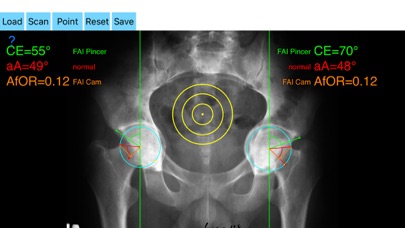

The drawn lines between points, allows app to estimate in radiographs, Center-Edge Angle (CE), α - angle (aA) and the anterior femoral offset ratio (AfOR). The measured values are compared with values from normal reference database. In case the measured angles are beyond the normal range, the hip is categorized as normal, dysplastic, borderline dysplastic hip and the type of femoroacetabular impingement (FAI) deformity namely cam type, pincer type or mixed is printed over the screen accordingly. Measures by the app are not affected by the X-ray projection.